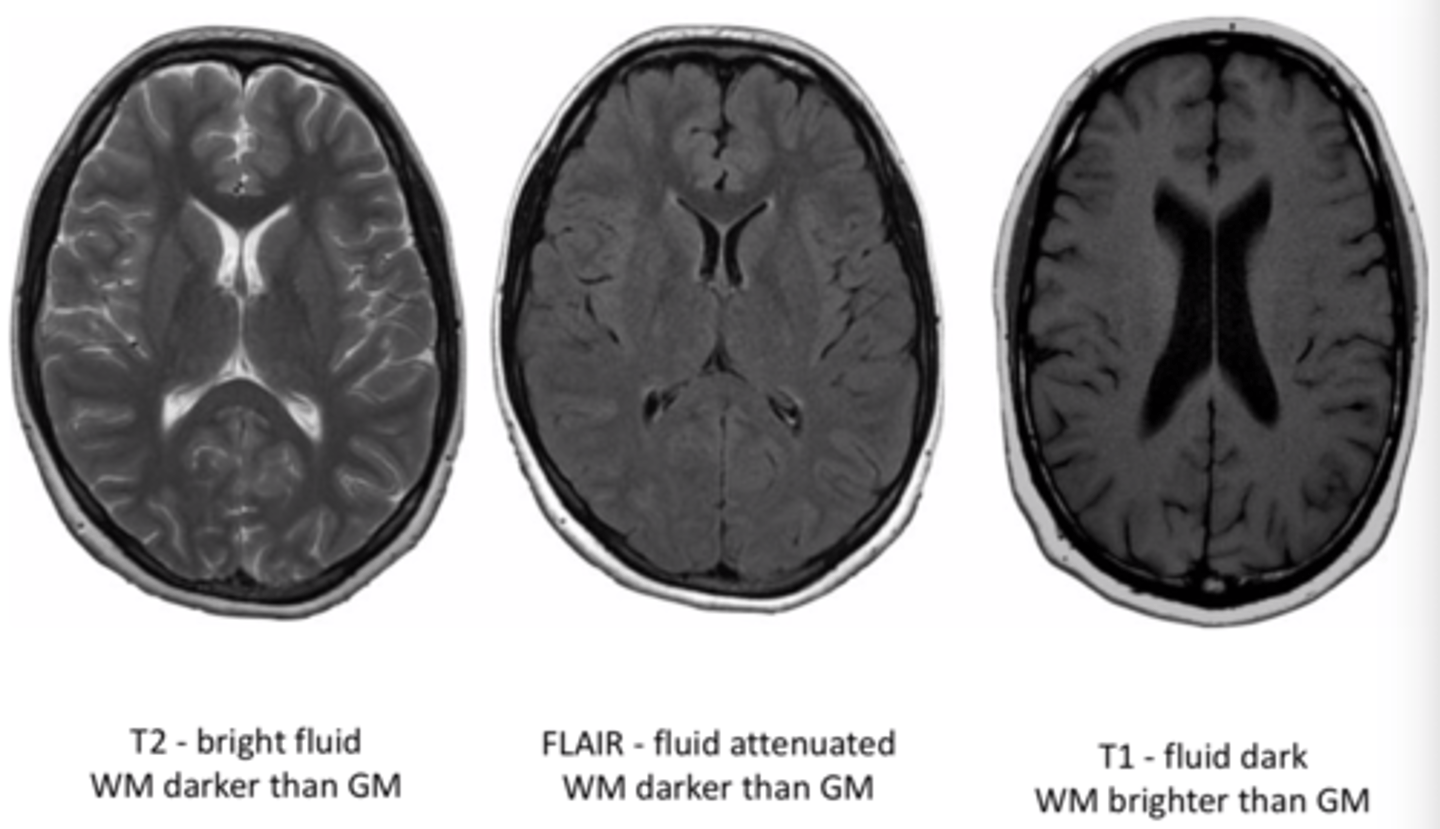

MRI T1 images

Fat is white

Water is dark

MRI T2 images

Fat is dark

Water is white

MRI flair images

Similar to T2, but CSF is dark